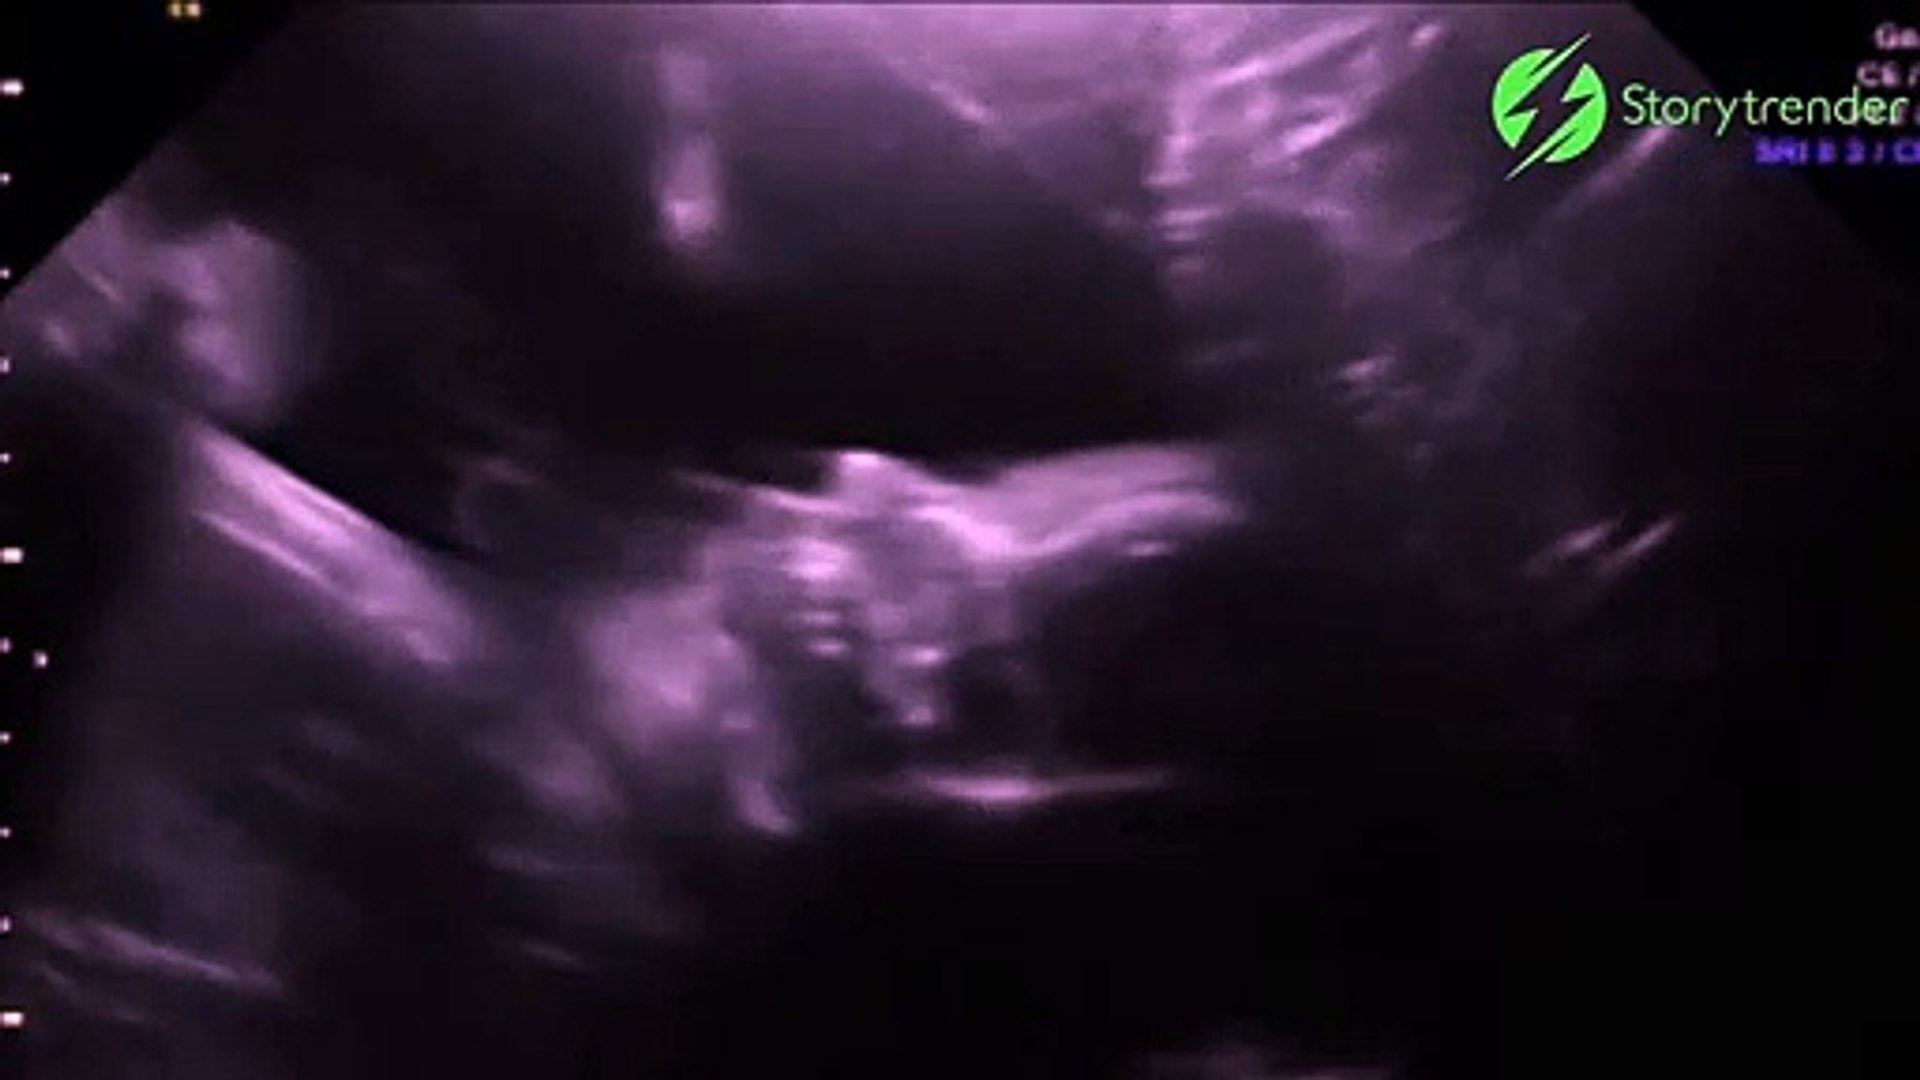

Leur bébé, dont la naissance est prévue pour le 5 mars, a semblése tourner vers la caméra et leur faire coucou de la main N'en croyant pas leurs yeux, les futurs parents ont demandé à l'intervenante de rembobiner la vidéo pour mieux voirCoucou on fait des bébé ? J'ai commandé un nounours qui fait coucou, et depuis j'ai toujours rien , j'ai reçu un mail du site , en rapportant la commande sur l'excuse d'un petit retard Malgré ça j'ai toujours rien j'ai envoyé deux mails et j'ai pas de réponse N'achetez rien sur ce site Internet Répondre Annuler l'envoi Ajouter une image (facultatif) Etre notifié des nouveaux commentaires

Pour celles et ceux qui découvrent, Crescendo, c'est l'association d'éveil musical de Lannion, et pour un aperçu de ce qui s'y fait, on peut lire ceci Quant à l'Ecocentre, c'est un lieu superbe! La durée d'incubation est faible (11 à 12 jours), ce qui fait que le jeune coucou éclot simultanément ou même avant les jeunes de l'hôte A l'éclosion, le jeune coucou possède le réflexe d'éjecter hors du nid tout ce qui s'y trouve de façon à se retrouver seul à bord La nature l'a doté d'une dépression en haut du dos qui recueille et éjecte coup sur coup les oeufs ou lesVidéo bébé fait coucou lors d'une échographie La future maman, entamant sa 28ème semaine de grossesse, a réalisé une échographie de contrôle Accompagnée de son compagnon, le couple a eu droit à un joli geste de leur bébé ce dernier leur a fait coucou!